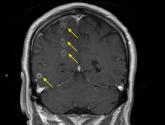

ArticleBrain abscesses in a 60-year-old manAuthor:Stella Pak, MDPublish date: September 4, 2018The lesions were not from compromised immunity, but from septic hematogenous spread of an odontogenic infection.Read More